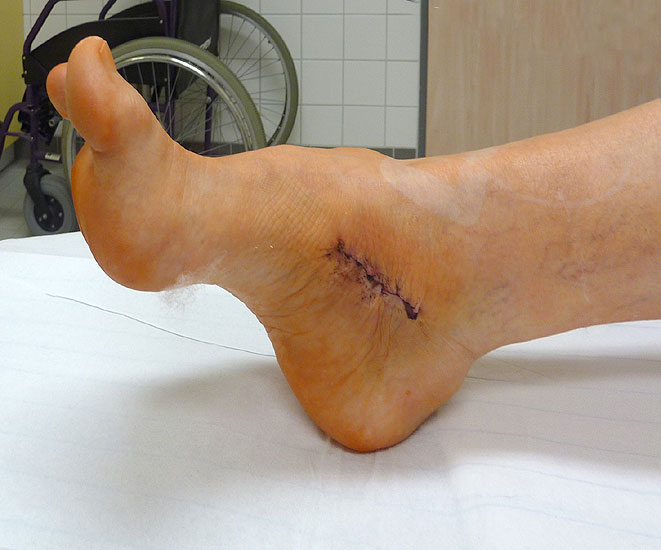

OP nach Steindler: Die verdickte und kontrakte Plantarfaszie wird komplett durchtrennt. Gelegentlich ist bei Kontraktur der Beugesehnen auch der calcaneare Ansatz des M. flexor digitorum brevis mit abzulösen. Dieser Eingriff steht zu Beginn der Hohlfußkorrektur. Der Zugang erfolgt über einen kleinen medialen Schnitt, über welchen sie die Plantarfaszie gut erreichen lässt (Abb. 23 und 24).

Zum Lesen der Bildbeschreibung und zur Vollansicht bitte die Bilder anklicken. Bilder: M. Walther